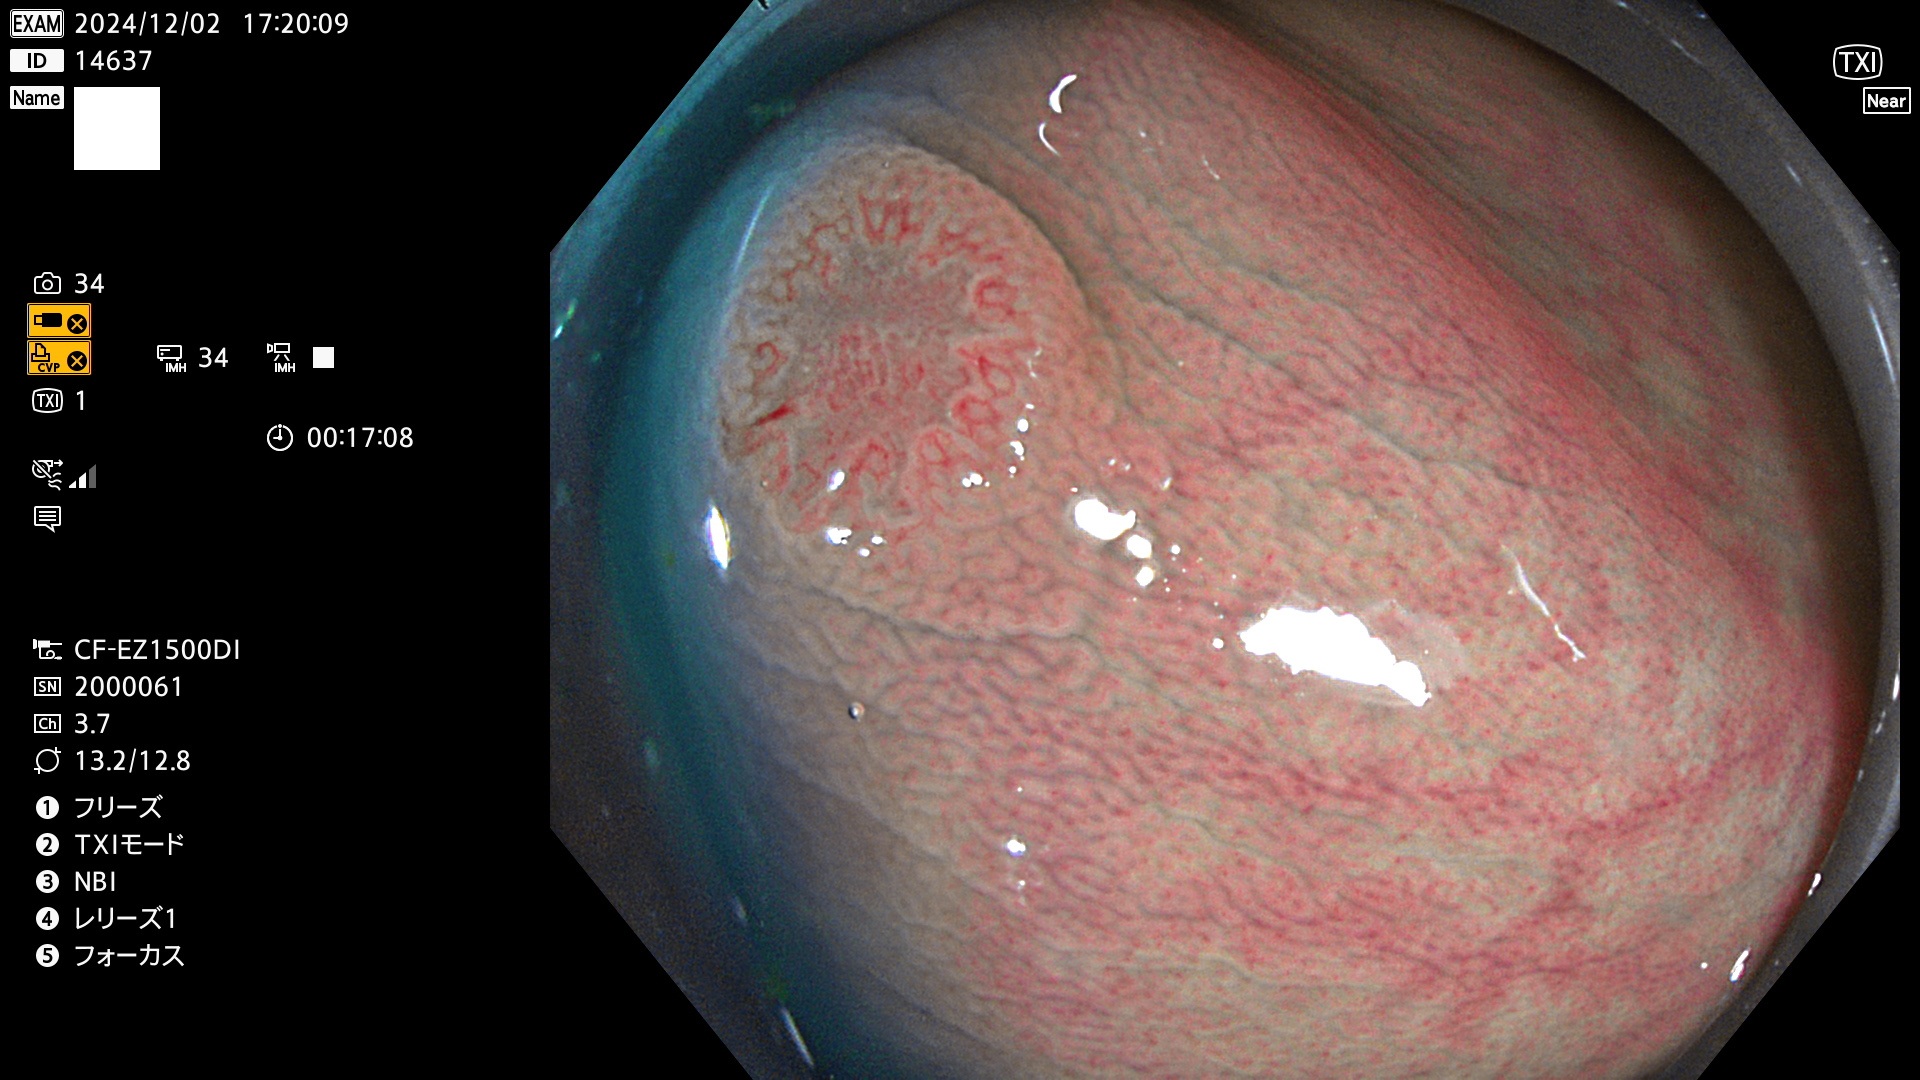

今週のUb、Uc型腺腫

完全に平坦な物をUb、陥凹している物をUcと呼びます。最も発見が難しく危険な病変です。

毎週の検査(木・金・土・日)に発見されたUb、Uc型・腺腫を、その週の日曜の夜にUPし1週間、提示します。

抽出の対象期間 2024年11月28日〜12月2日の5日間(60件の検査)9件 (9/60=15%)